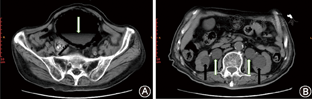

患者,男,81岁。因进行性排尿困难3年余、加重4 d于2020年10月8日入院。排尿困难加重后伴明显的腹痛、腹胀。查体:下腹膨隆,触痛(+),叩诊呈鼓音。既往糖尿病史13余年,平素虽规律口服盐酸二甲双胍肠溶片降糖治疗,但未监测血糖,入院时空腹血糖12.3 mmol/L。血常规示白细胞19.7×109/L,中性粒细胞0.907;血生化示尿素氮16.47 mmol/L,肌酐233.3 μmol/L,钾2.90 mmol/L;尿常规示尿潜血(+),尿蛋白(++),尿葡萄糖(++),尿镜检红细胞293个/HP,白细胞809个/HP。泌尿系超声检查示,双肾积水,双侧输尿管扩张,前列腺增生。腹部立位X线片:盆区类圆形气体密度影,边缘毛糙,伴气液平面。腹盆部CT平扫:膀胱壁内多发气体影,膀胱腔内可见气液平面,双侧肾盂、肾盏及输尿管扩张积液,双肾轻度萎缩,双侧输尿管末端可见气体影,前列腺增生(图1)。结合病史、临床症状、实验室及影像学检查,诊断为气肿性膀胱炎(emphysematous cystitis, EC)。于急诊留置导尿,可见大量气体排出,尿液浑浊,后腹痛、腹胀缓解;予盐酸莫西沙星抗感染治疗,同时行尿细菌培养+药敏试验,感染未见好转。

EC缺乏特异性的临床症状,主要有腹胀、腹痛、血尿、气尿、尿频、尿急、排尿困难、尿潴留、恶心、呕吐等。本例患者为老年男性,以腹痛、腹胀、排尿困难的症状就诊,查体下腹膨隆,触痛(+),叩诊呈鼓音,行腹盆部CT平扫后诊断为EC。因此,当老年糖尿病患者因以上临床症状就诊时,临床医生应考虑到EC的可能。EC的诊断主要依靠CT检查,腹部立位X线片检查在EC病变早期气体较少时常受肠管气体影响,容易漏诊。泌尿系超声检查由于受气体干扰,作用有限,但对是否合并上尿路病变有辅助诊断作用。而CT可清晰地显示膀胱壁、膀胱腔内及膀胱周围病变的程度和范围,典型表现为:膀胱壁内有泡状气体影,当部分气泡串连时,表现为串珠状;膀胱腔内可出现气液平面;膀胱壁外周可有气体带环绕,呈"气抱球样"改变[3]。同时,该患者CT检查还显示双侧肾输尿管积水、双侧输尿管末端积气、肾功能不全、双肾萎缩,前列腺增生,提示该患者膀胱腔内气体及尿液大量积聚导致膀胱内压增加,引起双侧肾输尿管积水、双侧输尿管末端积气,并且已影响了肾功能,如病情进一步恶化,可影响患者生命,所以应尽早诊治[4,5]。